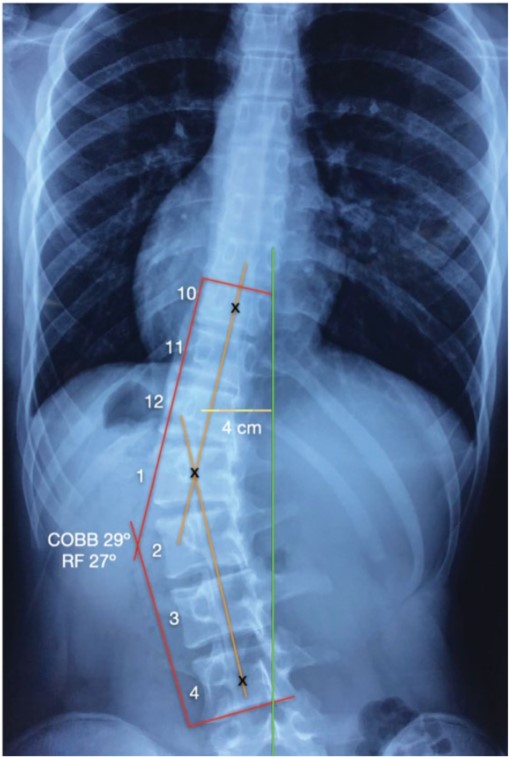

The patient brought full spine x-rays (Figure 1) to be assessed via the digitizing image data collection and radiographical interpretation software designed by ASPINE Systems. ASPINE Systems refers to a standard protocol for both spinal diagnostic procedures and noninvasive corrective rehabilitation treatments. The x-ray findings in the front view were: head tilted to the left from vertical line drawn from the middle of the vertebral body of T2 to the middle of the body of C2 creating a tilted angle of 5o degrees. The lumbar spine was shifted 4 cm to the left from center [9]. Cobb Angle gave a measurement of 29o degrees with a left convexity (using lower endplate of L4 and upper plate of T10). Modified Risser Ferguson measurement was 27o degrees using apex mid points of the vertebral bodies of L4, L1 and T10 [10,11].

Figure 1. Lumbar X-ray viewed posterior to anterior. Cobb angle of 29o/ Risser Ferguson of 27o; left translation (+TxT) by 4 cm from center.